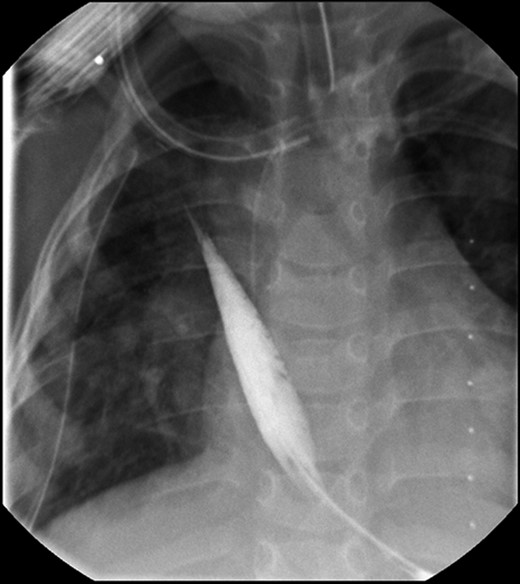

Daily tightening of her traction sutures was performed until the distal esophageal segment reached the chest wall (Fig. 2). The cervical esophagostomy was also sequentially lengthened and eventually internalized. Three traction suture revisions and two proximal esophageal lengthening operations were performed before esophageal continuity was re-established (46 days). Two subsequent anastomotic leaks occurred; 1 anastomotic leak was repaired surgically, whereas one subsequent leak was managed nonoperatively with a chest tube. Five dilations and, one, 13-day retrievable stent placement were needed for anastomotic narrowing. A comparative postoperative esophagram and intraoperative esophagram illustrated neither a stricture nor an anastomotic leak (Fig. 3). Total hospitalization was 112 days.

Fluoroscopic examination illustrating incremental ‘growth’ of the distal (lower) esophageal segment while the patient was undergoing external traction (Foker Stage 1). The contrast was injected through her existing gastrostomy tube. The metal dot refers to her esophagostomy; thus, can measure the distance between the ends of her esophageal segments.